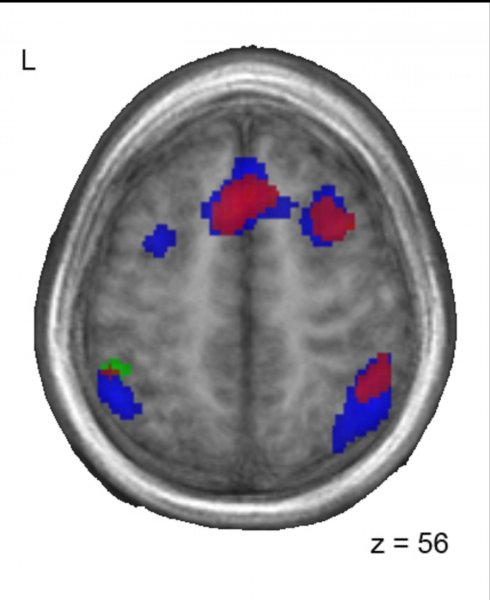

Patrones similares de actividad cerebral entre los bilingües chino-francés (rojo) y los adoptados (azul) cuando realizan una tarea con sonidos de francés. Imagen: Lara Pierce. Fuente: Universidad McGill.

A medida que los niños respondían a las palabras que escuchaban, los investigadores utilizaron imágenes de resonancia magnética funcional (fMRI) para mirar que partes de su cerebro se estaban activando.

Aunque todos los grupos realizaron las tareas igual de bien, las áreas del cerebro que se activaban difirieron entre los grupos. En los niños franceses monolingües sin exposición a China, se activaron las áreas del cerebro que se esperaba que intervinieran en el procesamiento de los sonidos del lenguaje, especialmente el giro frontal inferior izquierdo y la ínsula anterior. Sin embargo, entre los niños que eran bilingües (chino / francés) y los que habían sido expuestos al chino de pequeños y luego habían dejado de hablarlo, se activaron además otras áreas del cerebro, particularmente la circunvolución frontal media derecha, la corteza frontal medial izquierda, y el giro temporal superior bilateral.

Los investigadores observaron que los niños chinos que habían sido adoptados por familias francesas monolingües y ya no hablaban chino, y por tanto eran funcionalmente monolingües en el momento de la prueba, todavía tenían cerebros que procesaban el lenguaje de una manera similar a los niños bilingües.